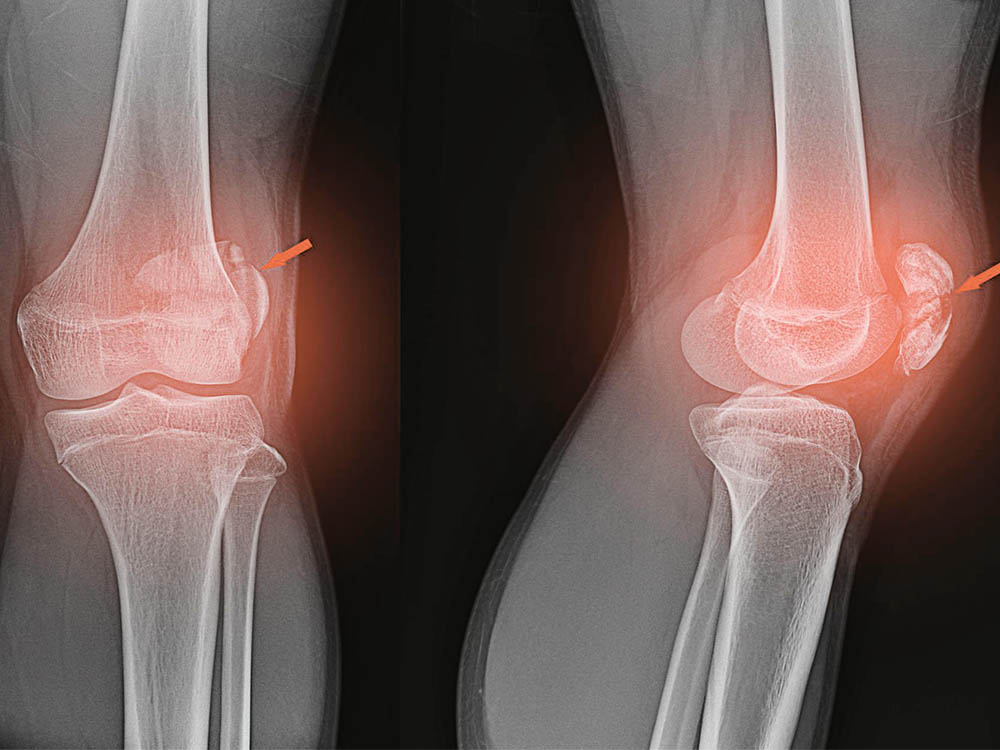

Заболевания и медицинские снимки: Жидкость в коленной чашечке

Раздел: Галерея прозрений